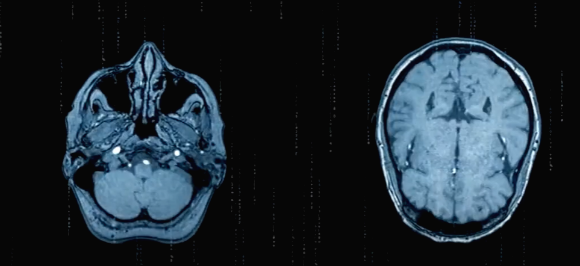

뇌동맥류의 진단

뇌동맥류를 찾아내는 방법은 크게 세 가지 방법이 있는데요.

CT 촬영을 이용한 혈관조영술과 MRI를 이용한 혈관조영술 그리고 엑스레이 촬영 후 혈관을 영상화하는 디지털 감산 혈관조영술 있습니다. 이와 같은 방법으로 뇌동맥류가 발견되었다면 동맥류의 원인, 형태, 환자의 건강 상태 등을 고려하여 경과관찰이나 치료를 결정하게 됩니다. 모든 사람에게 선별검사를 권하지는 않지만 뇌동맥류 위험요인이 있는 분들은 검사가 필요합니다.